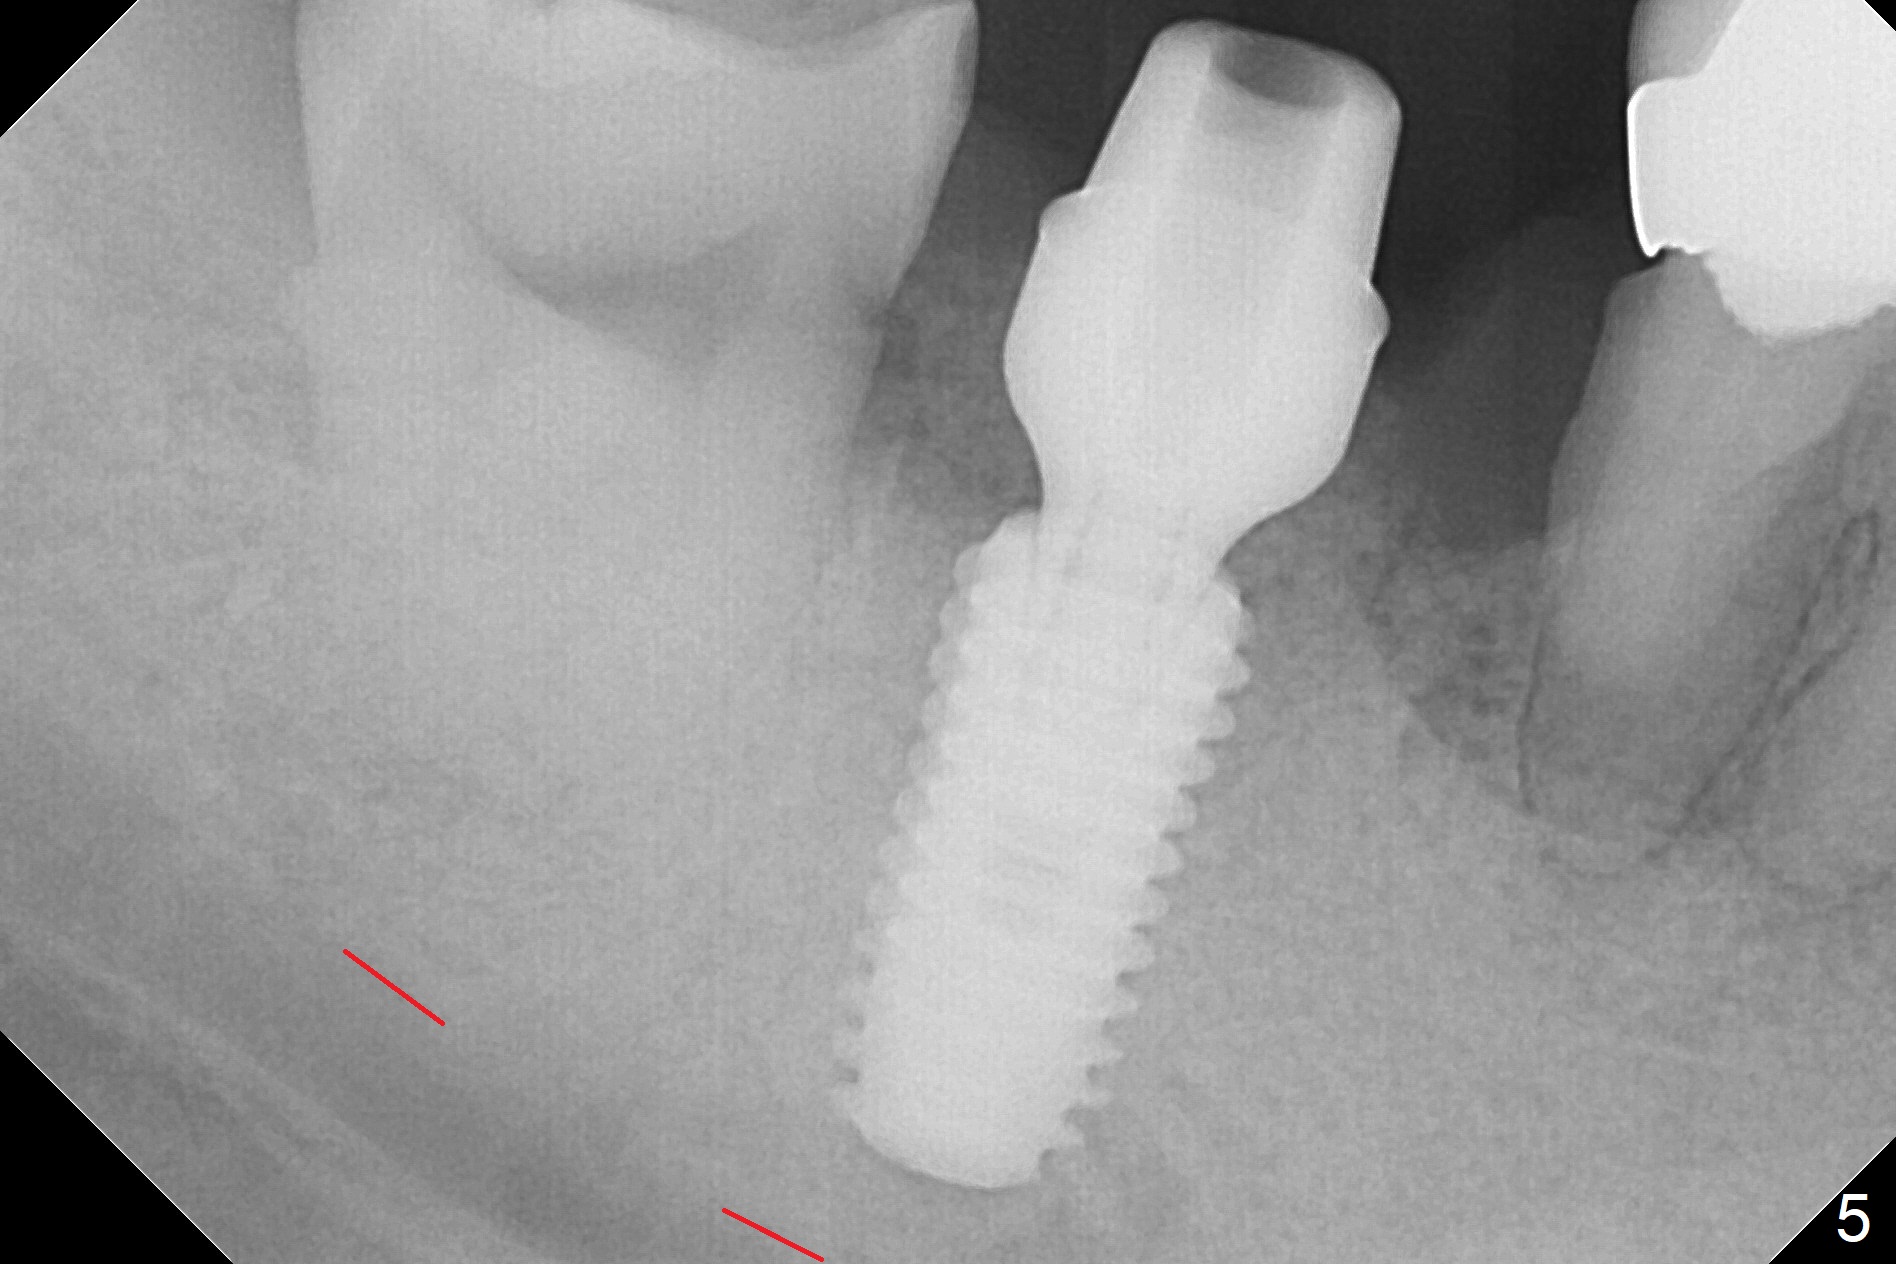

Although the tooth #30 has distobuccal root exposure (Fig.1 <), it is asymptomatic. In contrast the tooth #31 with the distoocclusal caries (*) is symptomatic. After use of 2 mm drill for 18 mm (lingual gingival margin), a calculated parallel pin is inserted (Fig.2 (D: 2 distal roots of the tooth #30)). It appears that a 11.5 mm long implant is appropriate for the site; a 5 mm cuff is expected. Following 4.8 mm drill, a 5.5x11.5 mm implant is placed initially (Fig.3) with an apical space (*) and clearance from the Inferior Alveolar Canal (red dashed line). The implant is placed deeper with placement of a 6.5x4(5) mm abutment and bone graft (*, Fig.4,5). After placement of collagen membrane over the graft, an immediate provisional is fabricated (Fig.6 P) with clearance from the opposing tooth (Fig.7 *). There is no bone loss 3.5 months postop (Fig.8). In fact the abutment has not been seated completely since its placement (Fig.4,5,8). The crown/abutment dislodges 3 years 3 months post cementation (Fig.9). The latter occurs for long incubation time because of opposing partial denture (Fig.10). After trimming proximal surfaces (Fig.11: arrowheads), the abutment remains incompletely seated (Fig.11) due to possible crestal bone interference (Fig.11 *). The smaller abutment by itself remains unseated (Fgi.12). One size small one is completely seated (Fig.13). Impression is taken. Two weeks later the abutment margin is supragingival. After screw torque at 20 Ncm, the crown is cemented with access hole. Excess cement is removed.